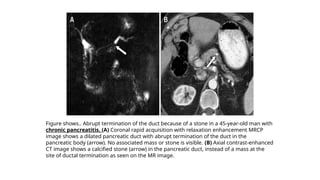

Figure shows.. Abrupt termination of the duct because of a stone in a 45-year-old man with

chronic pancreatitis. (A) Coronal rapid acquisition with relaxation enhancement MRCP

image shows a dilated pancreatic duct with abrupt termination of the duct in the

pancreatic body (arrow). No associated mass or stone is visible. (B) Axial contrast-enhanced

CT image shows a calcified stone (arrow) in the pancreatic duct, instead of a mass at the

site of ductal termination as seen on the MR image.